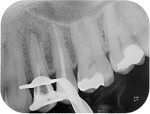

Post removal cases